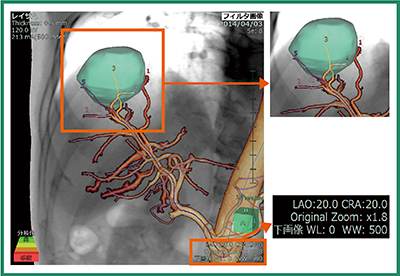

肝動脈化学塞栓療法(Transcatheter Arterial ChemoEmbolization:TACE)に代表されるようなInterventional Radiology(IVR)手技前に,治療対象となる腫瘍への栄養血管の解剖学的位置,また栄養血管の本数を同定することは,IVR手技中の造影剤投与量,被ばく線量の低減に効果的であると言われる。VINCENT Ver.5で搭載した“IVRシミュレータ”では,造影CT画像から疑似透視画像を作成し,腫瘍の半自動抽出,栄養血管の自動,手動抽出を行うことで,IVRの手技に必要な情報を表示する(図1)。

図1 IVRシミュレータで早期動脈相のCT画像から肝腫瘍に

到達する栄養血管をシミュレーションした画像例

造影効果の高い脈管領域を自動,半自動で抽出し,複数の栄養血管の同定や塞栓対象となる血管を明瞭に観察できる最適なX線管球角度(ワーキングアングル)を手動で設定する。IVRシミュレータを用いることで,従来の血管造影単独で行われるIVRと比較し低被ばく,少ない造影剤量でマイクロカテーテルの先端を進めることができる。